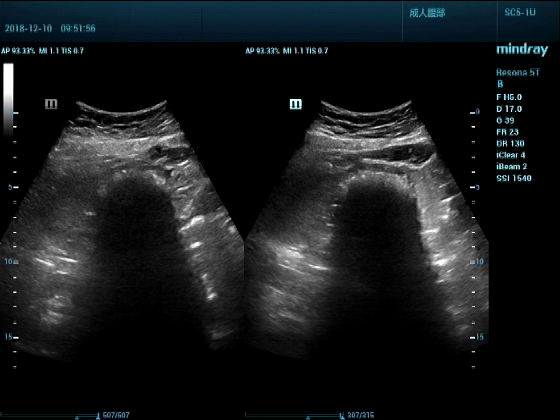

病例一:女,53岁,胃部不适一周来诊

超声可见:胃腔内见一小鸡蛋大强回声团块,后方伴强声影,位置活动。

问及病史吃山楂,柿子。

超声提示:结合临床考虑胃结石,治疗后复查